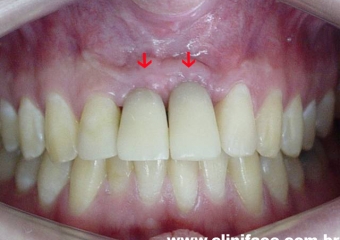

Próteses em porcelana instaladas

Sorriso final do caso terminado em agosto de 2007